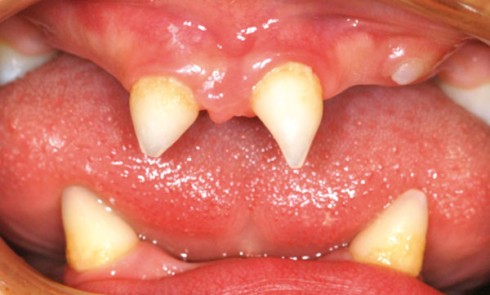

Article réservé à nos abonnés Dysplasie ectodermique hypohidrotique : prise en charge d’un cas clinique

Les dysplasies ectodermiques forment un groupe hétérogène de plus de 200 syndromes rares et complexes caractérisés par l’atteinte de plusieurs...